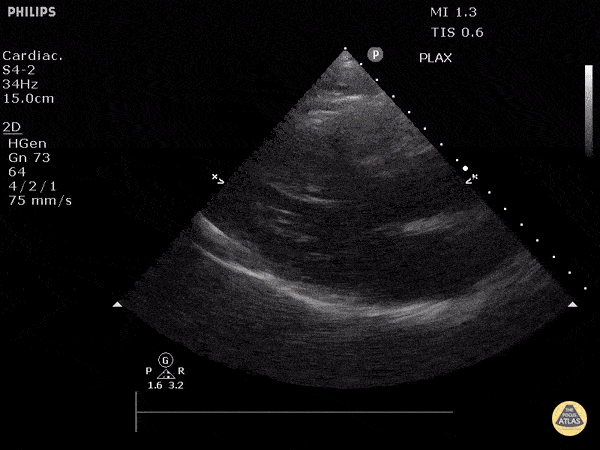

View: Unspecified Parasternal Long Axis Parasternal Short Axis Apical Four-Chamber Subcostal Four-Chamber Subcostal Inferior Vena Cava Right Upper Quadrant Left Upper Quadrant Suprapubic Longitudinal Suprapubic Transverse Subxiphoid Anterior Thoracic Phrenic